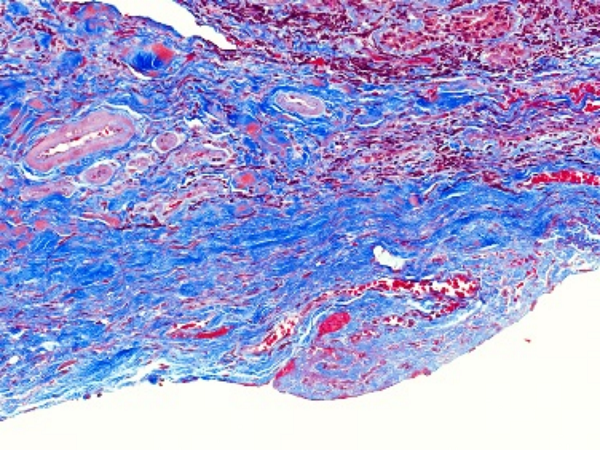

免疫组化(Immunohistochemistry,IHC)是一种利用抗原 - 抗体特异性反应来定位和定性组织细胞中特定抗原的技术,在病理学、肿瘤学等众多领域发挥着关键作用。**一、原理**1. 抗原 - 抗体反应 - 基于抗原与抗体之间的高度特异性结合。组织细胞中的蛋白质、多肽等抗原成分能够被相应的特异性抗体识别并结合

4008386992 立即咨询免疫组化(Immunohistochemistry,IHC)是一种利用抗原 - 抗体特异性反应来定位和定性组织细胞中特定抗原的技术,在病理学、肿瘤学等众多领域发挥着关键作用。

特殊染色是病理学和组织学中使用的一种染色方法,用于显示组织或细胞中的特定成分,这些成分在常规的苏木精 - 伊红(HE)染色中可能无法清晰地显示。以下是关于特殊染···...